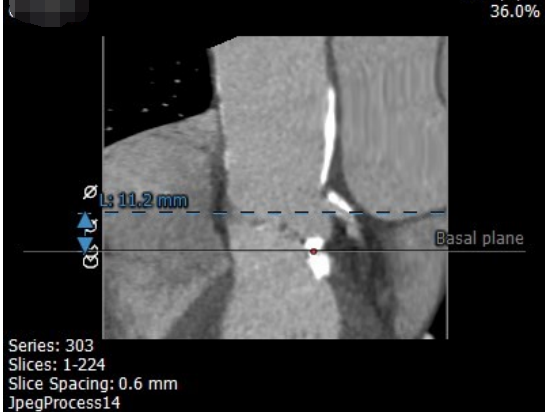

考虑到患者年龄较大,并发症多且复杂,心功能差,身形瘦小,无法耐受常规的开胸手术,经过术前综合评估,我们建议患者实施经导管主动脉瓣置换术(TAVR),通过介入的方式,将组装好的主动脉瓣经导管置入体内,完成主动脉瓣的置换。

经过内外科团队讨论,由于右桡动脉已经闭塞,在不影响后续经股动脉实施TAVR手术的前提下,治疗团队决定先由心内科经左桡动脉途径,处理冠状动脉主干和左前降支钙化性病变,同时处理左锁骨下动脉钙化性病变。十几个小时后再由心外科行TAVR手术。